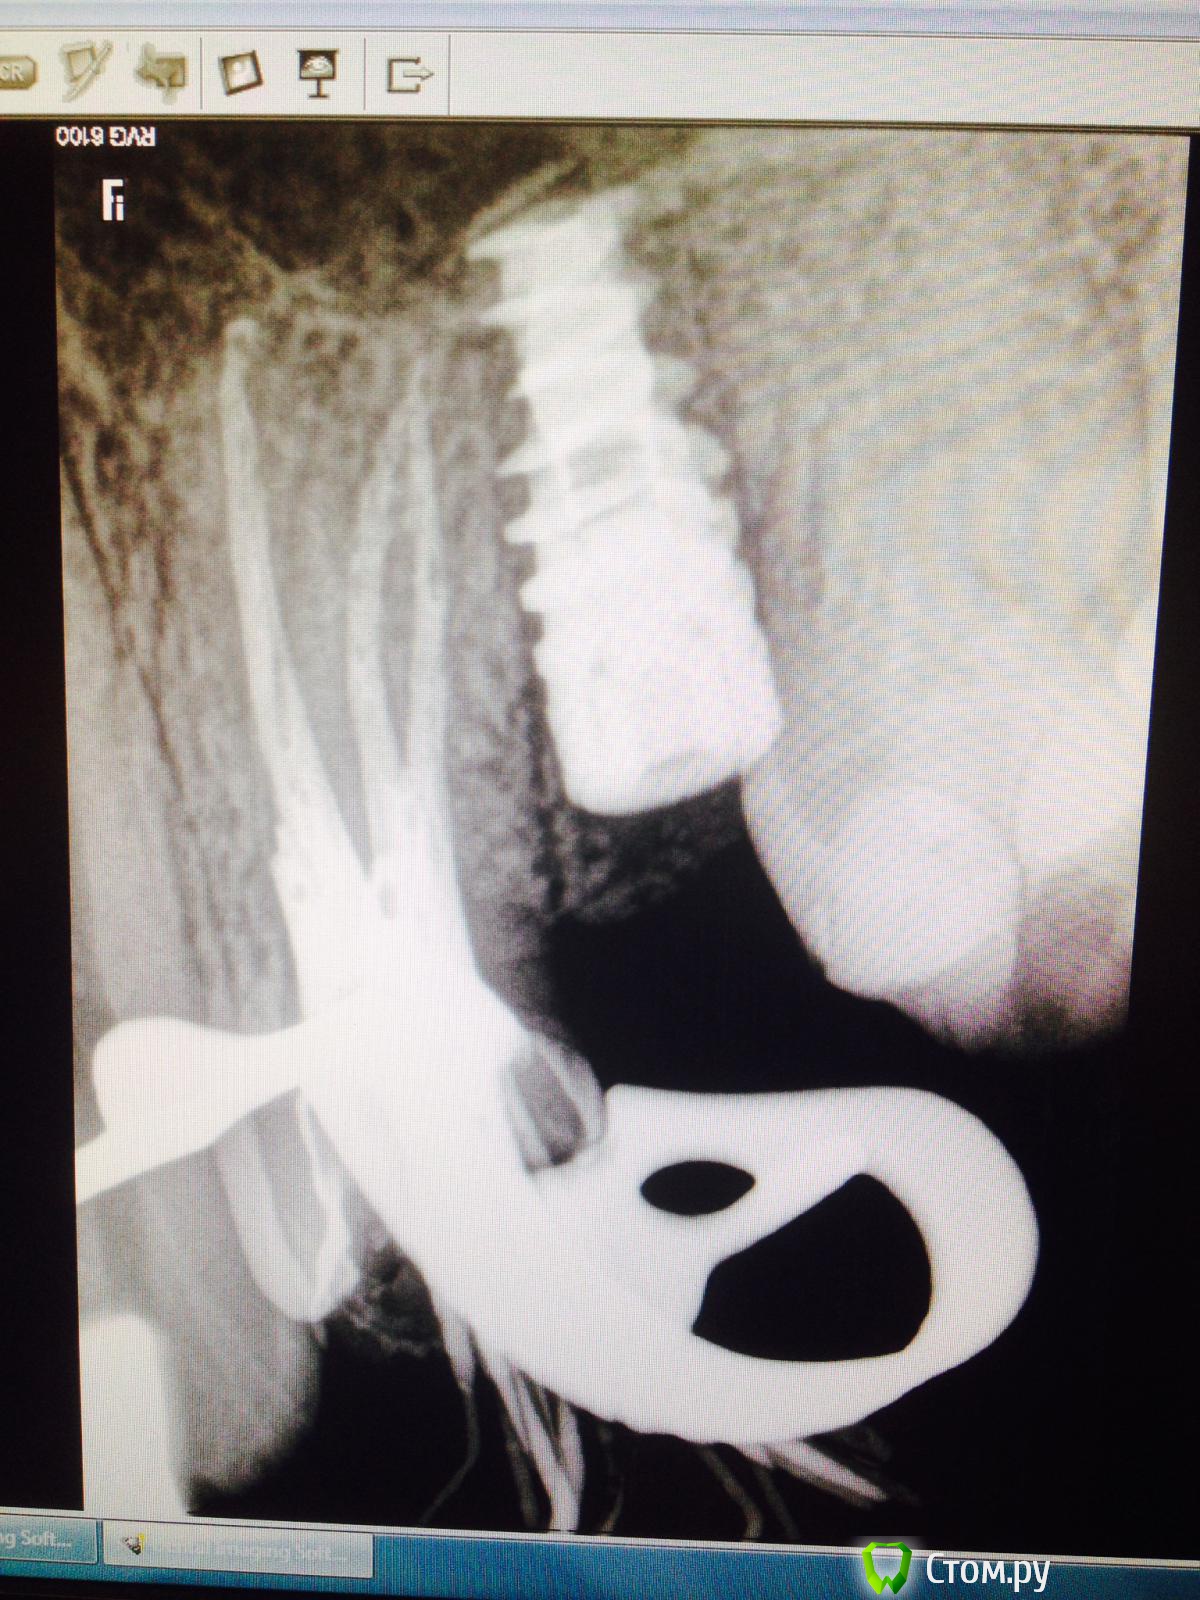

Тимур86 Опубликовано 17 июня, 2014 Поделиться Опубликовано 17 июня, 2014 Господа!пациентке около 4 месяцев тому назад был установлен имплантат в области 25!альфа спи 4.2/10,кт нету под рукой,но проблем с костью небыло вообще (10/10мм по-моему)!в общем имплантация как по учебнику!торк 30-35,сверлил не больше 1000 об.все зажило норм!пришла на фдм-поставили!после установки фдм жаловалась на дикие боли в области импланта!как при пульпите!всю голову сломали,26 по пульпиту пролечили(там пломба глубокая была)в общем вчера,недели через 3 после установки фдм,ортопед вытащил пальцами имплантат...вопросы:1-по какой причине это могло случиться?если дезинтеграция-то почему при установке фдм не вылетел?торк был 30!2-если предположить что боли все-таки были связаны с имплантатом,то что же там так могло болеть на протяжении почти 2- недель? Ссылка на комментарий

КДБ Опубликовано 17 июня, 2014 Поделиться Опубликовано 17 июня, 2014 рентгенологически и до лечения 6го были изменения в области имплантата 1 Ссылка на комментарий

Тимур86 Опубликовано 17 июня, 2014 Автор Поделиться Опубликовано 17 июня, 2014 рентгенологически и до лечения 6го были изменения в области имплантатау меня часто какие-то изменения рентгенологически в первые месяцы!связывал это с ремоделировкой кости... Ссылка на комментарий

КДБ Опубликовано 17 июня, 2014 Поделиться Опубликовано 17 июня, 2014 у меня часто какие-то изменения рентгенологически в первые месяцы!связывал это с ремоделировкой кости...явно носит воспалительный характер и 1 снимок и еще выраженней 3й Ссылка на комментарий

Тимур86 Опубликовано 17 июня, 2014 Автор Поделиться Опубликовано 17 июня, 2014 не может быть причиной материал в гайморовой выведенный? Ссылка на комментарий

Тимур86 Опубликовано 17 июня, 2014 Автор Поделиться Опубликовано 17 июня, 2014 явно носит воспалительный характер и 1 снимок и еще выраженней 3йну допустим...почему боли после фдм начались?причем очень сильные!от чего там вообще сильной боли взяться? Ссылка на комментарий